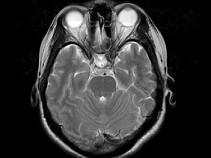

女,41岁,阵发性头痛伴恶心、呕吐20余天,CT影像如图,最可能的诊断为 ( )

• A.双侧筛窦息肉

• B.双侧筛窦息真菌感染

• C.双侧筛窦过敏性炎症

• D.双侧筛窦炎

• E.双侧筛窦未见明显异常

答案: D